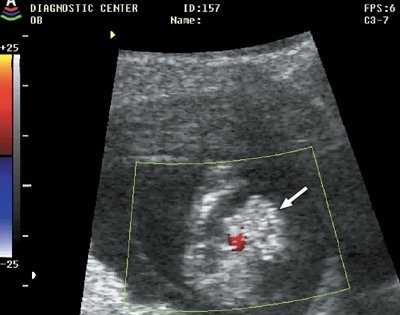

Рис. 5. Мегацистис (стрелка), беременность 11 недель 3 дня.